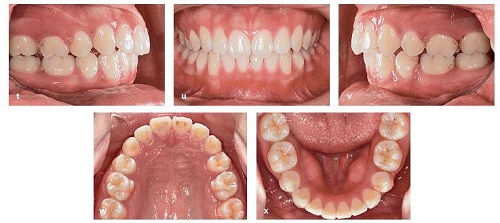

Bệnh nhân tiếp tục thay đổi khay trong suốt khi điều trị tiếp tục. Tại tháng 19, đeo khay được hoàn thành. Tất cả các mắc cài và attachment được gỡ bỏ, và khay bổ sung được đeo để điều chỉnh chi tiết và hoàn thiện (Hình 13-16t đến 13-16x).

Hồ sơ cuối cùng. (hh và ii) So sánh các phim cephalometric trước và sau điều trị. Lưu ý sự kéo ra sau của răng cửa và cải thiện độ nghiêng răng cửa.

Cả hai cung răng đều được làm đều tốt với khoảng nhổ răng đã đóng và khớp cắn hoàn thành trong mối tương quan loại I với cắn phủ, cắn chìa bình thường. Chụp phim toàn cảnh panorama cho thấy các chân răng song song trên vị trí nhổ răng.